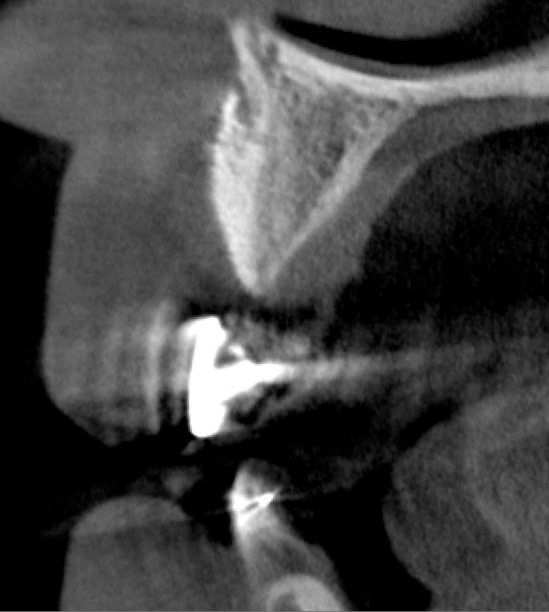

After 3 months of post-orthodontic stabilization, a cone-beam computed tomography scan was taken to re-evaluate the results and plan the future treatment sequence. Tomographic images clearly showed vertical gains in alveolar height, including in the edentulous area corresponding to tooth No. 7 (Figure 10 through Figure 12). The apex of tooth No. 8 was forced-erupted beyond its socket and could be visibly located within the soft tissue.30,33

Fig 10. Tomographic images of teeth Nos. 6 (Fig 10), 7 (Fig 11), and 8 (Fig 12) clearly showed vertical gains in alveolar height, including in the edentulous area corresponding to tooth No. 7. The apex of tooth No. 8 was located within the soft tissue because it was force-erupted beyond its socket.

Figure 10

Fig 11. Tomographic images of teeth Nos. 6 (Fig 10), 7 (Fig 11), and 8 (Fig 12) clearly showed vertical gains in alveolar height, including in the edentulous area corresponding to tooth No. 7. The apex of tooth No. 8 was located within the soft tissue because it was force-erupted beyond its socket.

Figure 11

Fig 12. Tomographic images of teeth Nos. 6 (Fig 10), 7 (Fig 11), and 8 (Fig 12) clearly showed vertical gains in alveolar height, including in the edentulous area corresponding to tooth No. 7. The apex of tooth No. 8 was located within the soft tissue because it was force-erupted beyond its socket.

Figure 12